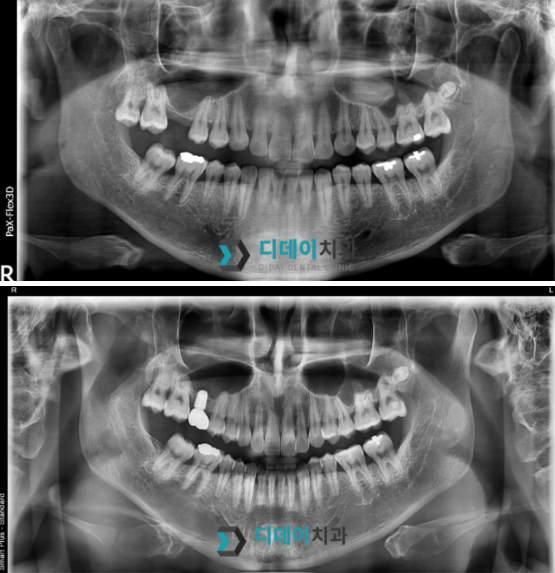

어금니 임플란트 치료를 위해 내원하신 환자분입니다.

오른쪽 위 어금니 발치한 상태로 내원하셨고

상악동 함기화로 인해 치조골이 부족한 상태였기때문에

상악동 거상술을 같이 진행했습니다.

2024-07-08